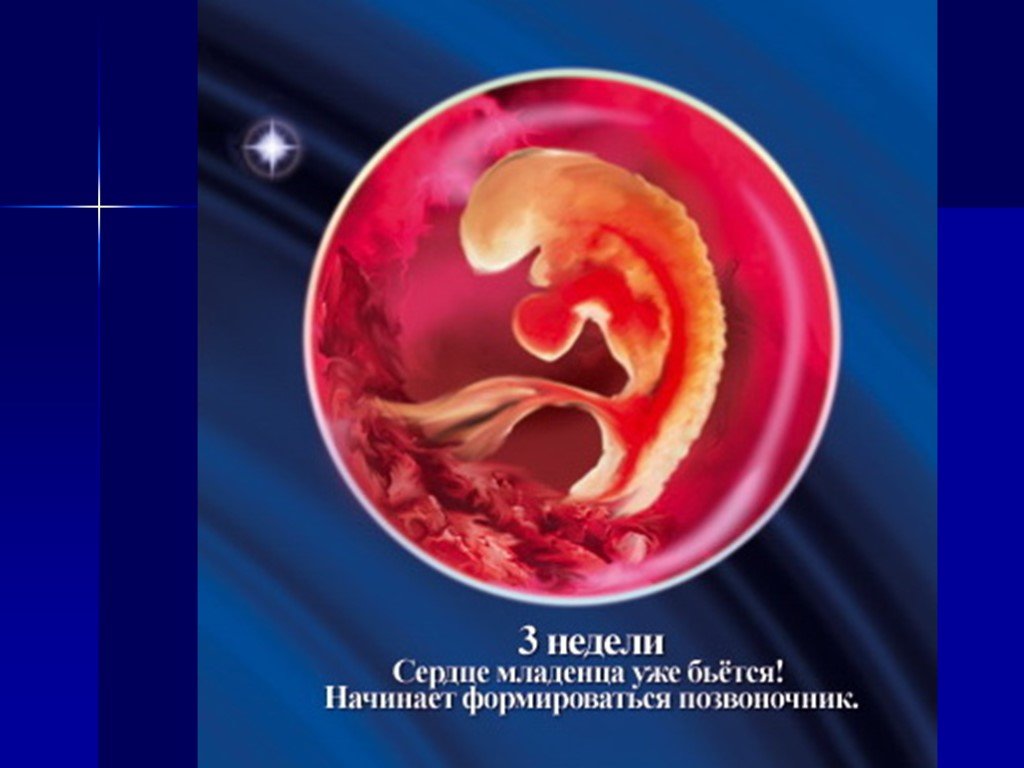

Развитие эмбриона: Что происходит на 3 неделе беременности